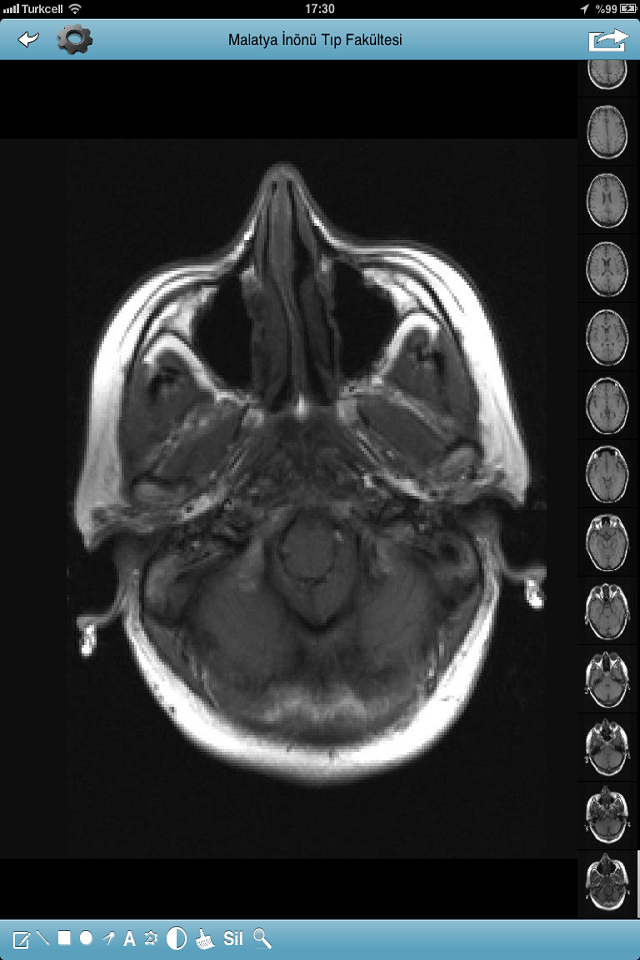

PACS ekranı eklendi